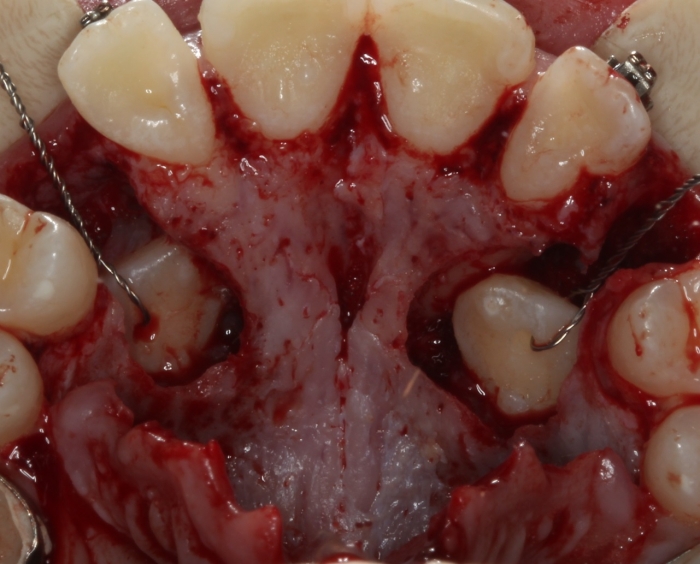

Cirurgia com fio de aço instalado para tracionamento dos caninos permanentes